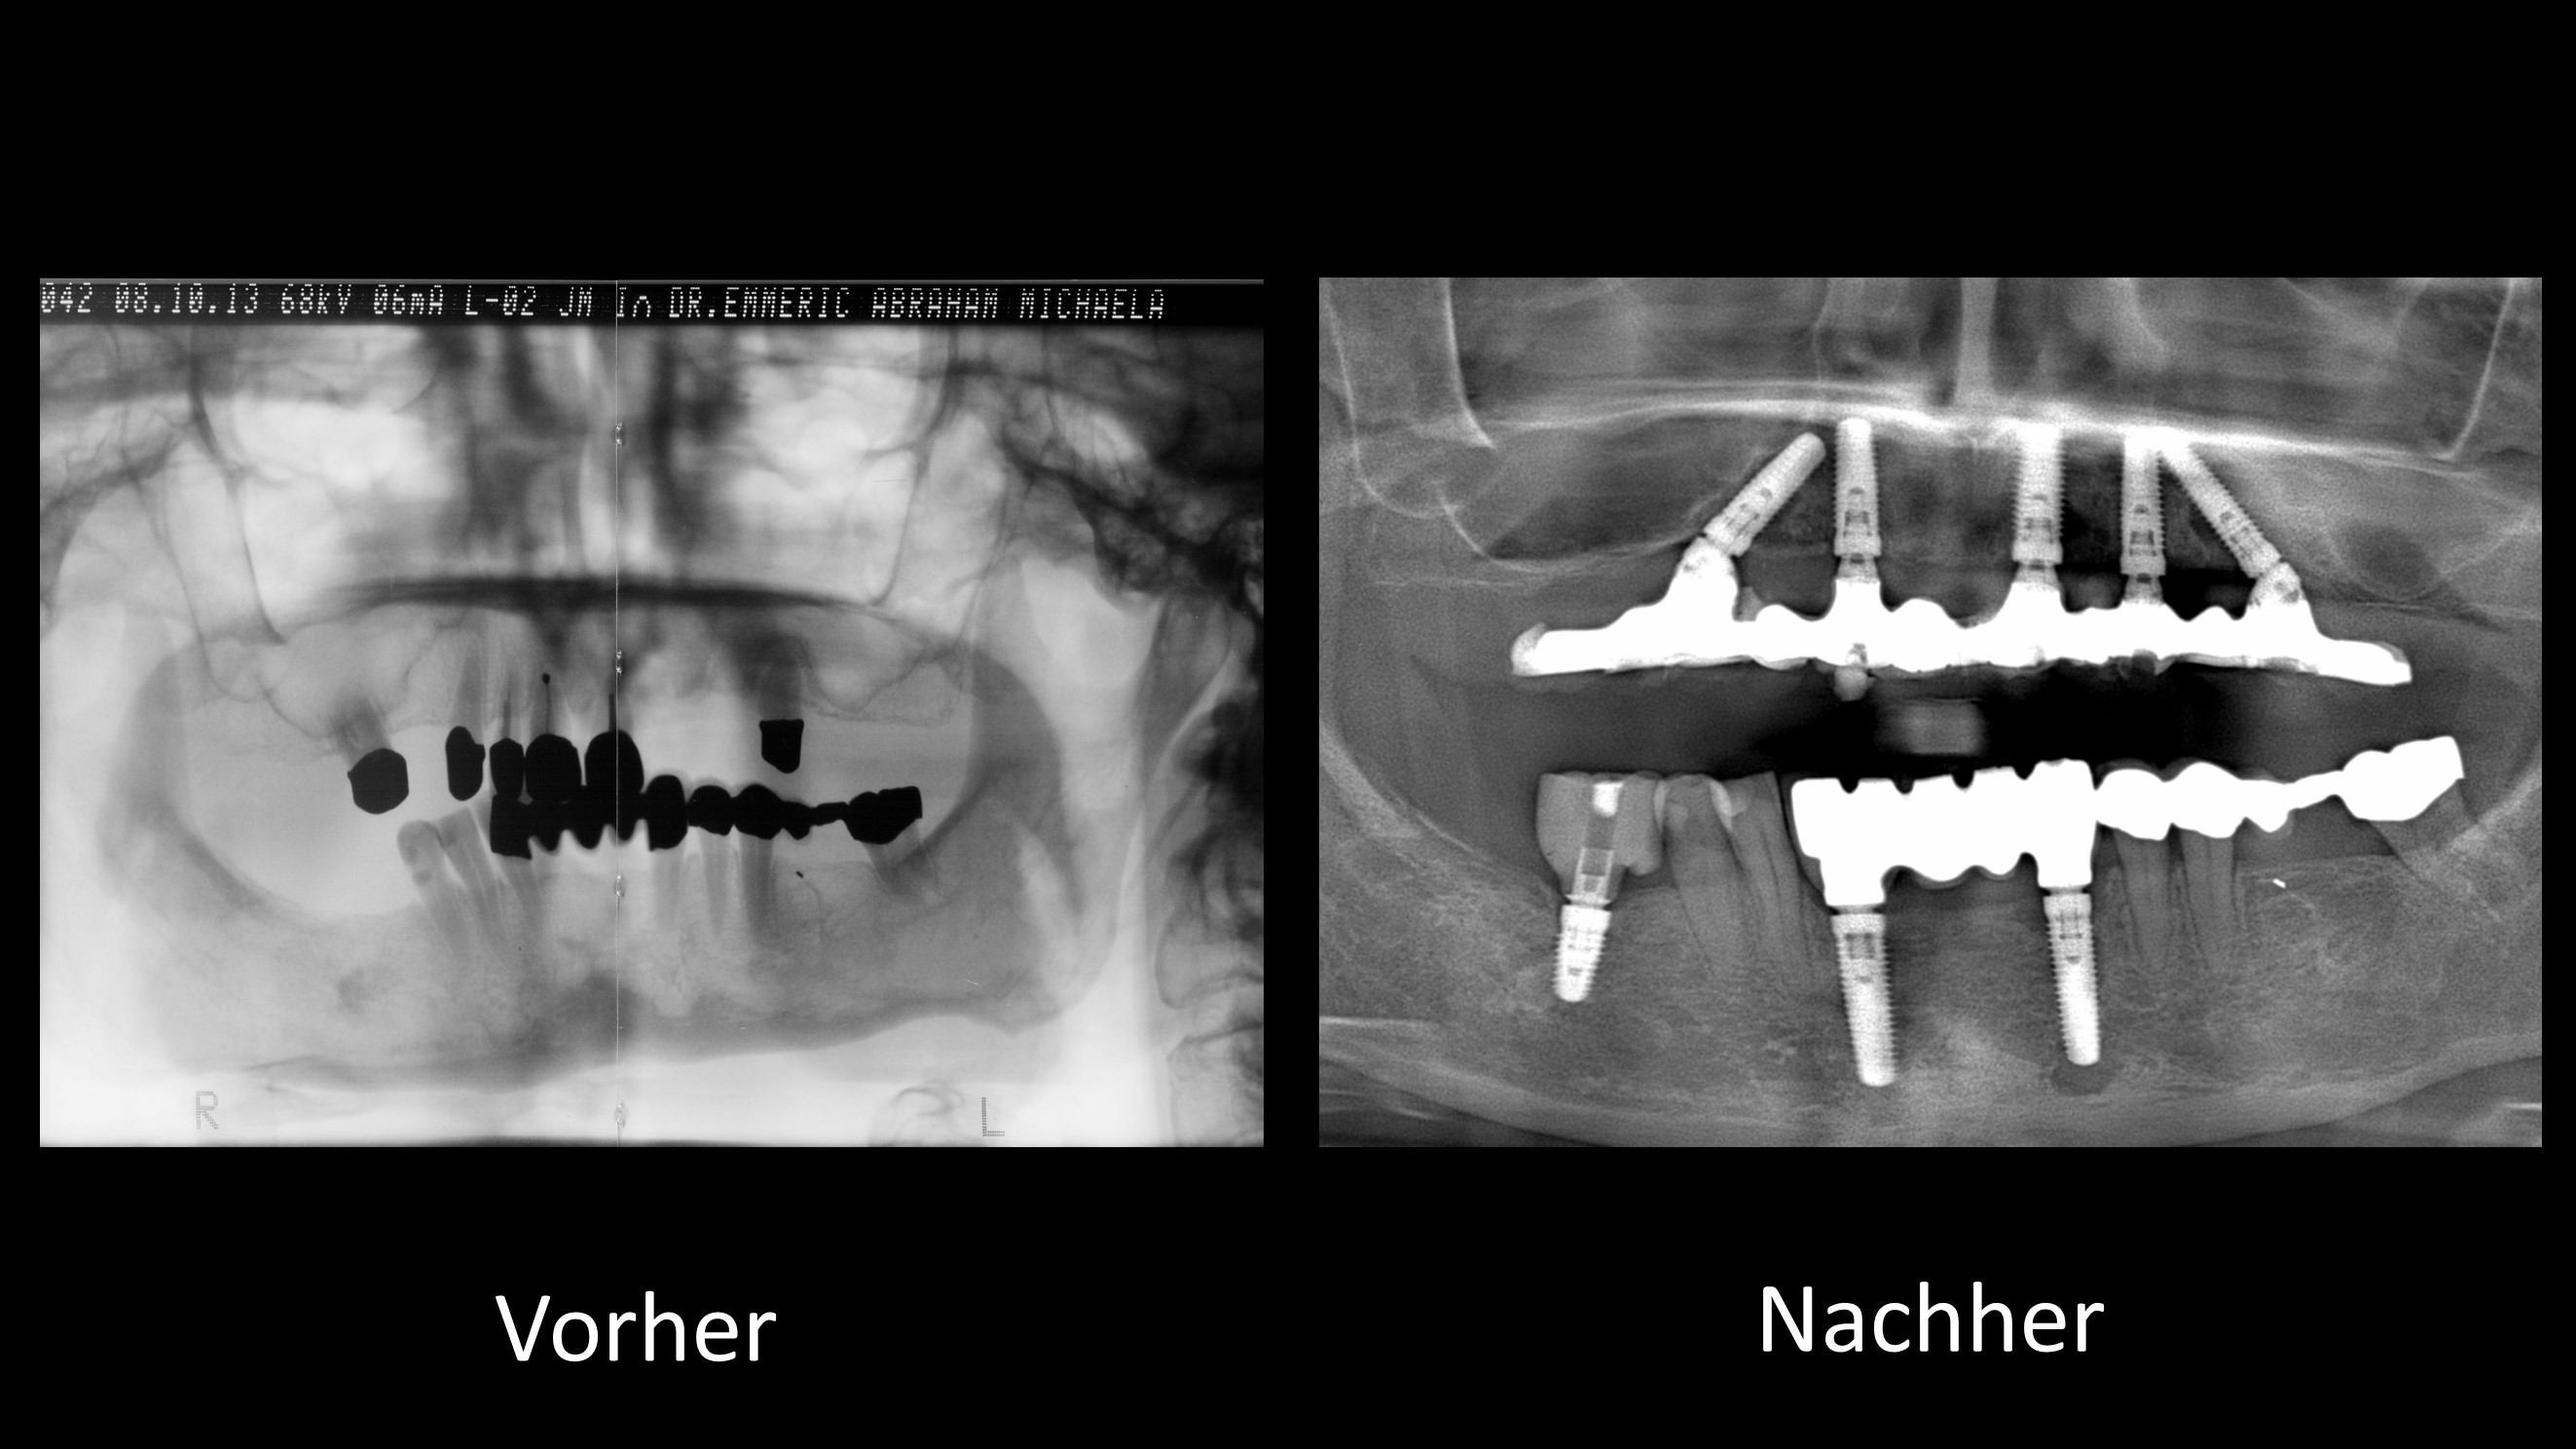

Vorher-Nachher-Röntgenbilder:

Ganzkiefer-Brücken auf 4 und mehr Implantaten

Bei unserer Sofortimplantat-Methode werden die hinteren Implantate meist schräg eingesetzt

und sofort mit den neuen Zähnen versorgt:

Durch die Schrägstellung sind einerseits längere Implantate möglich und andererseits werden gleichzeitig anatomisch wichtige Strukturen geschont (Unterkiefernerv, Kieferhöhle). Zusätzlich resultiert die Schrägstellung in einer statisch günstigeren Belastung und einer besseren Verteilung der Implantate (weiter hinten im Kiefer).